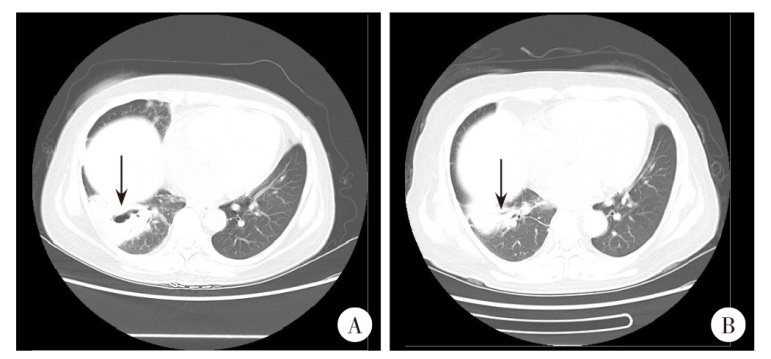

The patient was a 38-year-old female farmer from Xiangning County, Linfen City, Shanxi Province. She was diagnosed with nephrotic syndrome in 2016 and systemic lupus erythematosus in 2021. In October 2024, the patient was admitted to the Department of Rheumatology and Immunology due to recurrent fever. Laboratory tests revealed pancytopenia, inverted albumin-globulin ratio, elevated IgG levels, coagulation abnormalities, positive anticardiolipin antibodies and splenomegaly, and sputum fungal cultures indicated Candida albicans infection. Chest CT scans on October 29 showed scattered inflammation in bilateral lungs with cavity formation in the right lower lobe. On October 31, bone marrow punctures displayed one megakaryocyte and widespread platelet distribution in blood marrow smears, and Leishmania amastigotes (Leishman-Donovan bodies) were observed across whole bone marrow smears, prompting patient’s transfer to the Department of Infectious Diseases. On November 5, serum samples were sent to Shanxi Provincial Center for Disease Control and Prevention, where the rK39 rapid immunochromatographic test yielded a positive result. On November 6, metagenomic next-generation sequencing (mNGS) of bone marrows detected 66 596 Leishmania species DNA sequences, including 1 668 L. infantum sequences with relative abundance of 52.02%. Symptomatic treatments were therefore given, including continuous oxygen therapy, transfusion of leukoreduced red blood cells, anti-infection therapy, fluid replacement, correction of hypoalbuminemia, and hemostasis. On November 4, amphotericin B cholesterol sulfate complex was administered intravenously at 50 mg via an intravenous pump, and the dose was adjusted to 100 mg on November 5 and further escalated to the 150 mg (full dose) on November 6. The patient was discharged after the discomfort symptoms gradually subsided. A follow-up examination on December 9 showed excellent antiprotozoal efficacy, with no Leishmania amastigotes detected and the pulmonary cavities disappeared. Subsequent follow-ups indicated no recurrence in the patient.